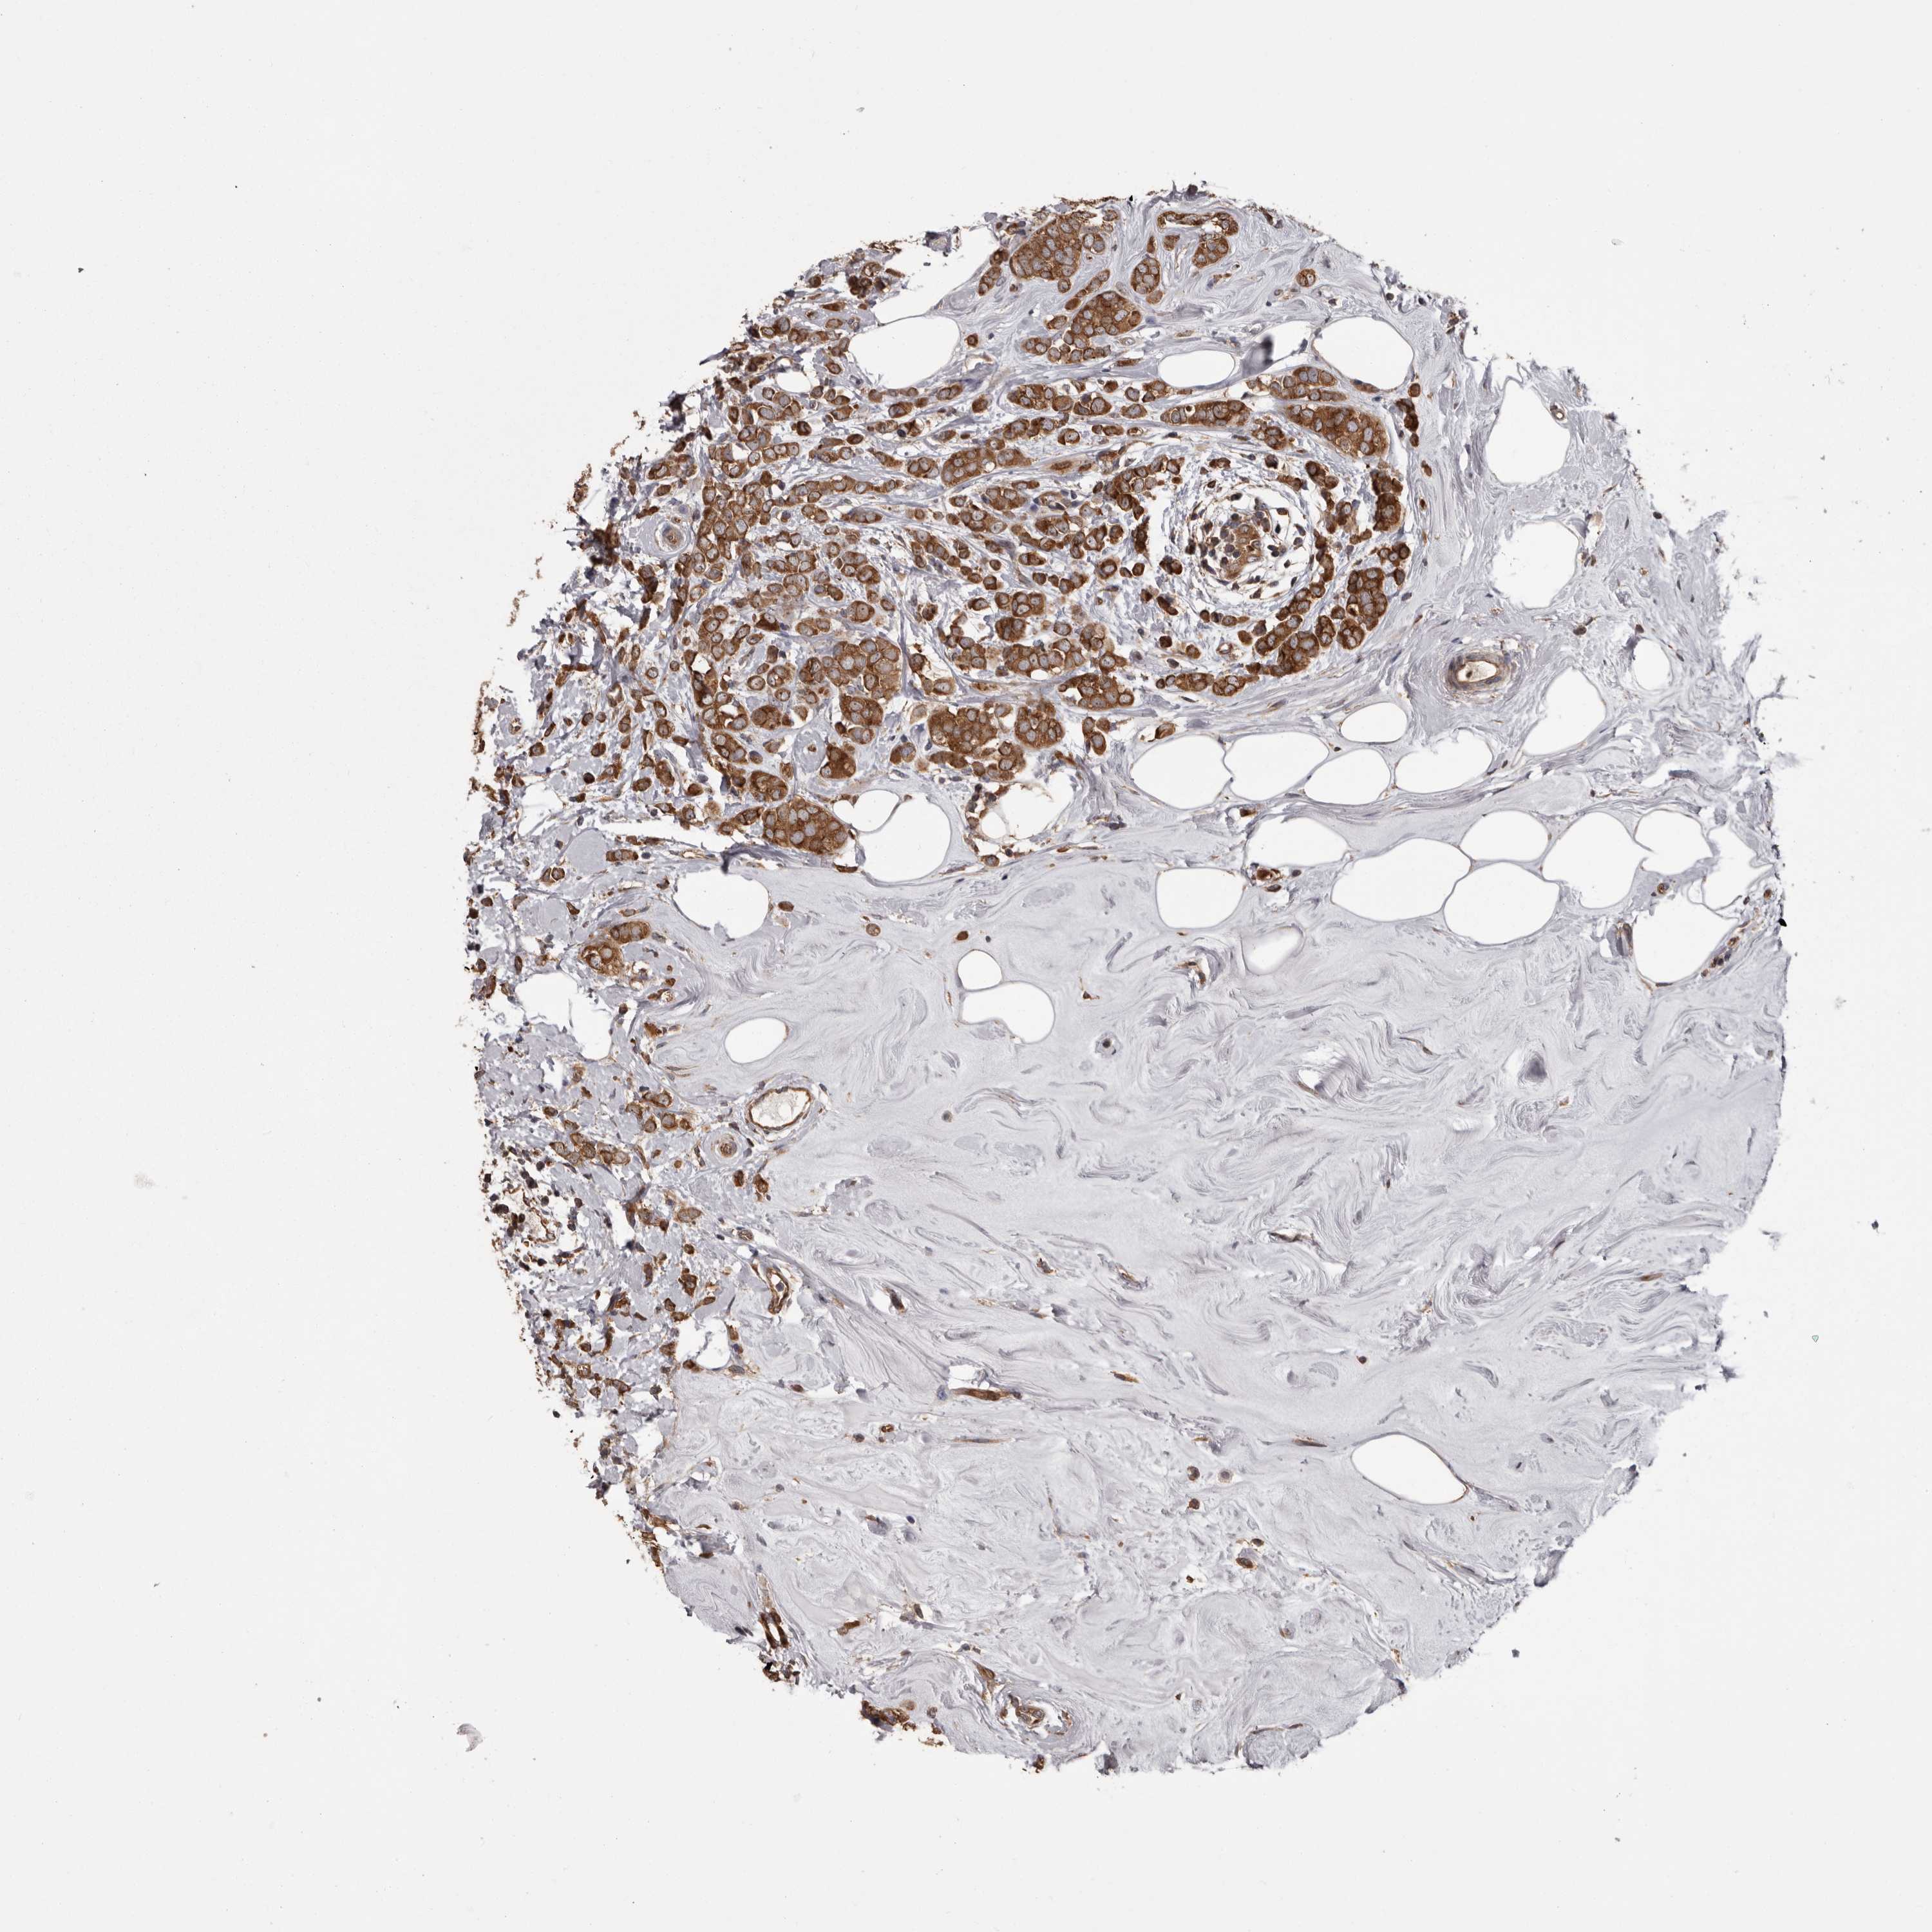

CANCER BREAST CANCER Show tissue menu

BRCA TCGA BRCA VALIDATION PROTEIN EXPRESSION